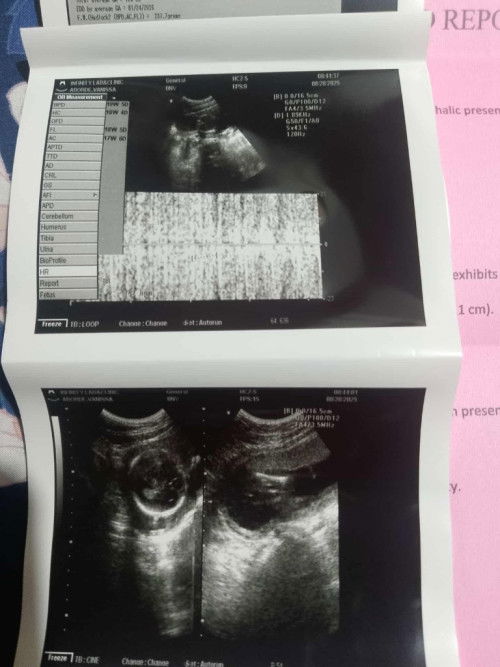

normal ang findings. age of gestation ay 18W5D based sa measurements ni baby. EDD ay jan. 24. naka cephalic si baby, good for normal delivery. mataas ang inunan, which is good. anterior placenta, meaning ay nasa harap ang inunan.